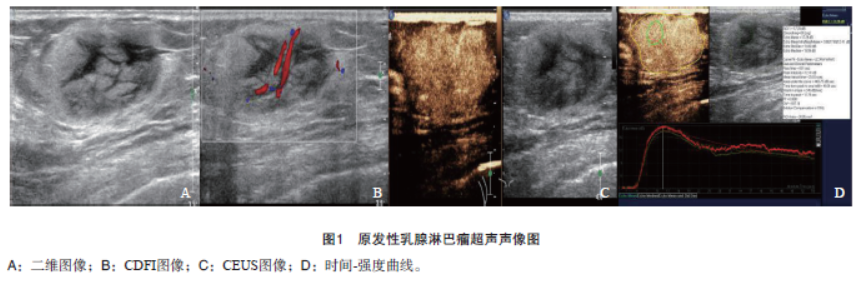

超声检查:右侧乳腺1—2点方向探及大小约3.40 cm×1.70 cm混合回声,高低回声相间,外形规则,边界清,周围可见高回声晕,后方回声增强(图1A);彩色多普勒血流显像(color Doppler flow imaging,CDFI)显示肿块内可探及丰富血流信号,其动脉频谱阻力指数(resistance index,RI)为0.80(图1B);腋窝未见明显增大淋巴结声像图。超声造影(contrast-enhanced ultrasound,CEUS)示造影剂注入10 s后病灶呈向心性增强,15 s达到峰值,最大强度为16.70 dB;病灶呈均匀增强,与周围组织分界清,肿块CEUS增强范围与二维超声相比未明显增大,其内见粗大迂曲增强血管(图1C、D)。

超声提示为右侧乳腺混合回声病灶,乳腺影像报告和数据系统(Breast Imaging Reporting and Data System,BI-RADS)分类4a级。超声引导下对肿块穿刺活检,病理学与免疫组织化学检查:非霍奇金,弥漫大B细胞淋巴瘤

,非生发中心来源亚型。